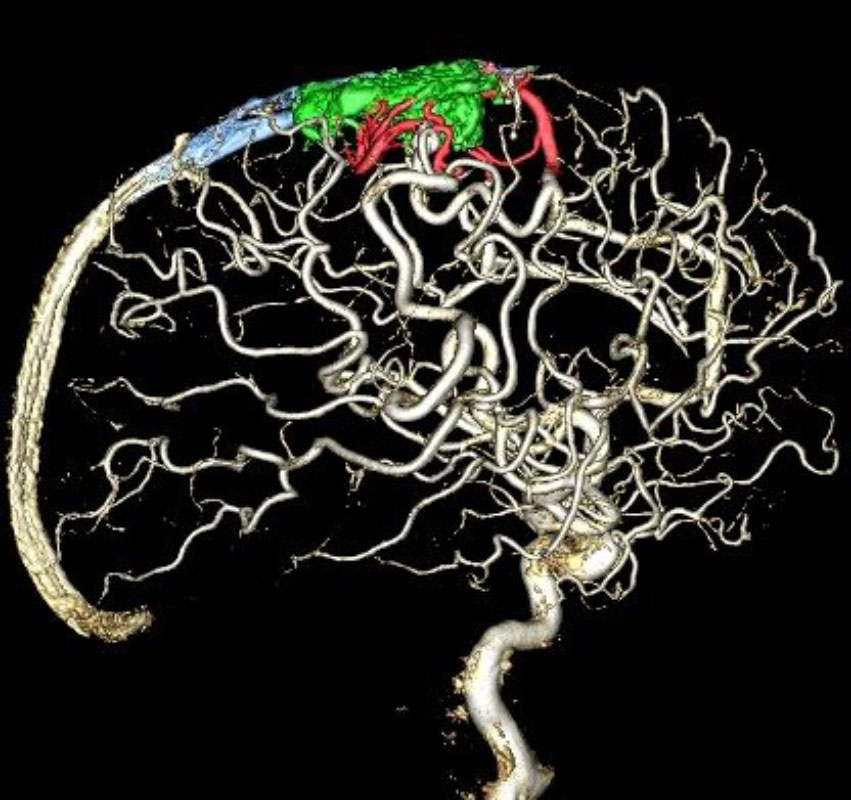

脳動静脈奇形

血管塞栓術

松田/濵田/元永